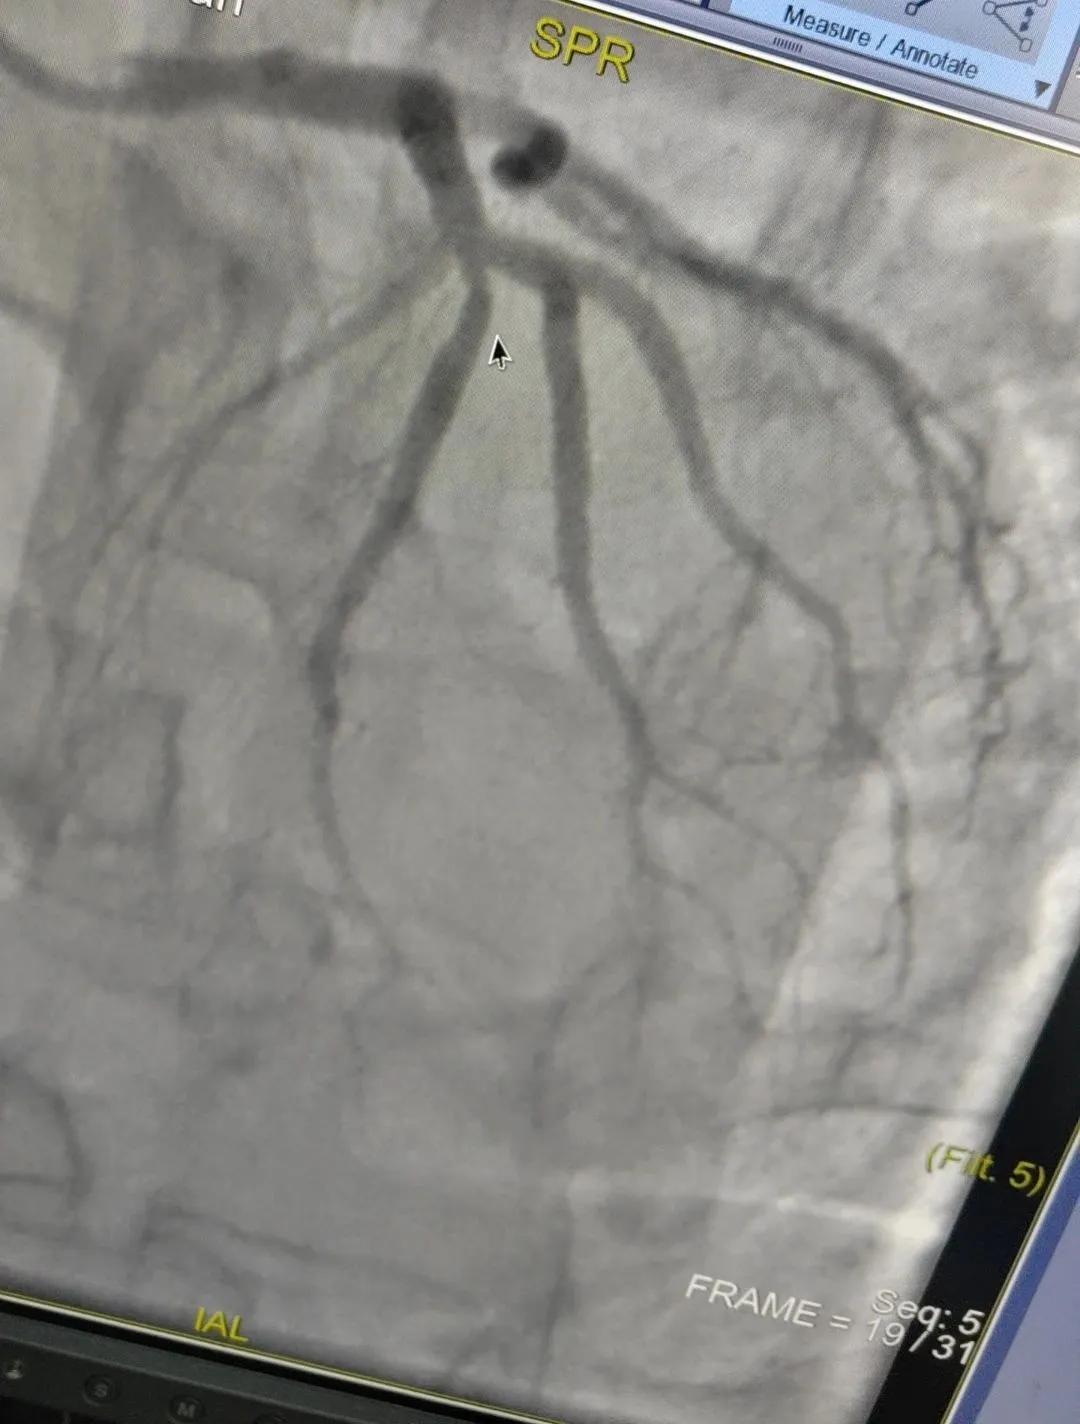

近日,漯河市中醫(yī)院成功開展了一例心腦血管聯(lián)合造影的手術(shù)。

患者男,37歲,兩周前無明顯誘因突發(fā)頭昏,伴右側(cè)肢體無力來院就診,經(jīng)過對患者病情的評估以及心內(nèi)科和腦病科醫(yī)生聯(lián)合會(huì)診,需對患者進(jìn)行心腦血管聯(lián)合造影手術(shù)。由神經(jīng)內(nèi)科楊慶堂副主任與心血管內(nèi)科陳云副主任帶領(lǐng)各自的介入團(tuán)隊(duì)為該患者順利進(jìn)行了全腦血管造影術(shù)+心血管造影的介入檢查。

術(shù)中心血管造影顯示:LAD中段發(fā)出D1處可見約50%節(jié)段性狹窄,RCA中段狹窄約40%,PLA可見約70%狹窄病變。

腦血管造影顯示:左側(cè)頸內(nèi)動(dòng)脈嚴(yán)重遷曲,左側(cè)大腦前動(dòng)脈未顯影,左側(cè)大腦中動(dòng)脈M1中段以遠(yuǎn)未顯影,M1近段串珠樣嚴(yán)重狹窄,顱底可見少量煙霧血管,后交通動(dòng)脈未開放;右側(cè)頸內(nèi)動(dòng)脈嚴(yán)重遷曲。右側(cè)大腦前動(dòng)脈A1段嚴(yán)重遷曲。

心腦聯(lián)合造影不僅明確患者的病因和病變血管,還為下一步治療提供了有力的依據(jù)。